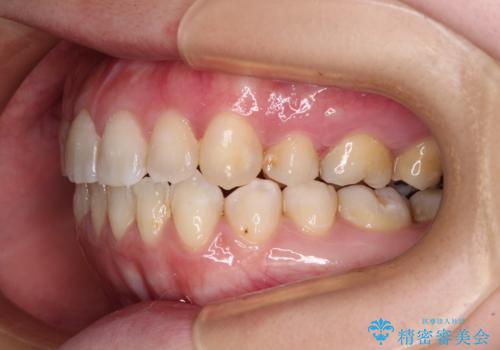

- 左上の八重歯と前歯のデコボコを気にして来院された患者様です。

下顎が左側にズレており、下顎前歯は1歯欠損していたため、左上小臼歯1本を抜歯し、ワイヤー装置にて矯正治療を行うこととしました。

骨格のズレと歯の欠損があったため、仕上がりの調整に時間がかかると思いましたが、舌突出癖の改善や顎間ゴムの装着をしっかりと行ってくださったので、速やかに治療を終えることができました。